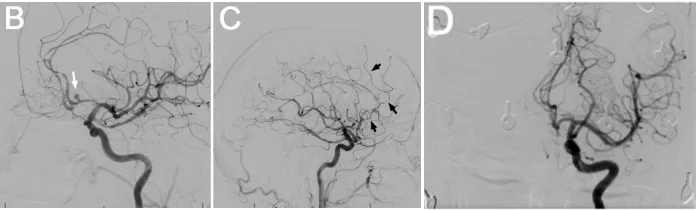

数字减影血管造影(DSA)显示,A1-A2端及前交通动脉瘤周围存在显著的放射性血管炎。DSA侧位像显示动脉瘤(箭头指示)。DSA侧位像显示放射性血管炎,表现为血管分支减少及多处血管狭窄(箭头指示)。DSA正位像显示2年前Wada试验时未见动脉瘤或血管炎性改变。血管造影亦证实存在放射性血管炎。

患者随后接受经右侧额部翼点入路开颅术行动脉瘤夹闭术,手术过程顺利。术后影像证实动脉瘤闭塞有效,无并发症。术后脑灌注成像显示一处术前已知的陈旧性脑梗死区域。患者术后接受随访监测,时长23.9个月。